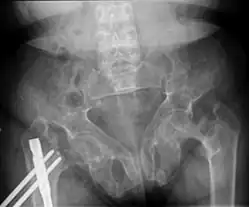

![Brown tumors in the pelvis and a hip fracture.[18]](./_assets_/X-ray_of_brown_tumors_in_the_pelvis_and_a_hip_fracture_in_renal_osteodystrophy.jpg) Brown tumors in the pelvis and a hip fracture.[18] Brown tumors in the pelvis and a hip fracture.[18]